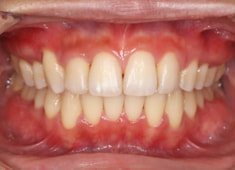

治療後(2年後)

治療開始から24ヶ月後